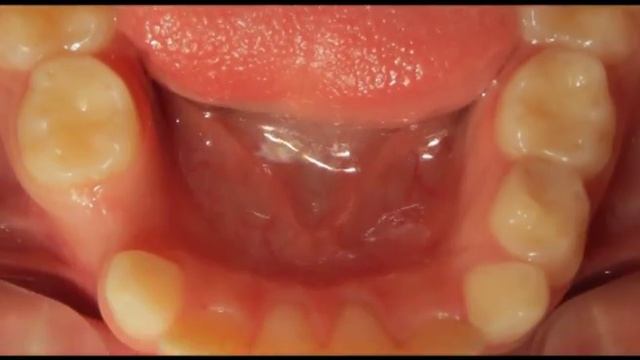

неправильный прикус. исправление прикуса. Трейнеры смотреть онлайн

05:24

неправильный прикус. исправление прикуса. Трейнеры

Мастерство и Талантливое Творение 62 просмотров